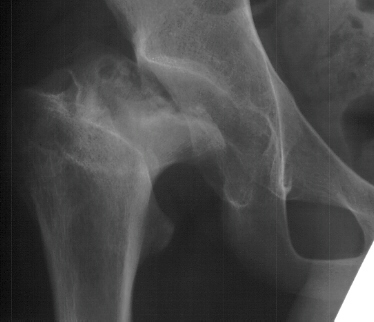

- 2 month Office Follow Up: Rt hip Xray: progressive destruction of capital

femoral epiphysis, cystic changes in metaphysis consistent with AVN.

- Age 6: Valgus osteotomy for subluxation and 2cm leg length inequality.

- Age 15: Valgus osteotomy for hip incongruity.

- Age 20: Hip arthroscopy. Hip fusion recommended.

This case is an example of untreated septic arthritis which caused avascular

necrosis of the proximal femur. The primary cause of this is undrained

septic hip. Repeated aspiration is not adequect treatment of a septic hip.